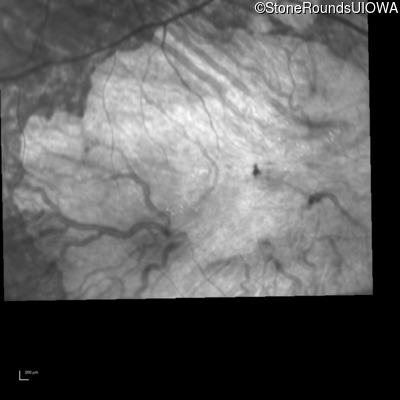

Infrared Fundus Photograph - Left - 10/400 sc

Exemplar